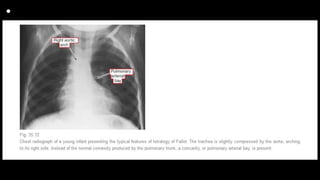

• Radiography

Cyanotic Tetralogy of Fallot

1. The heart size is normal or smaller than normal, and

pulmonary vascular markings are

decreased. “Black” lung fields are seen in TOF with pulmonary

atresia.

2. A concave main PA segment with an upturned apex (i.e., “boot-

shaped” heart or coeuren sabot) is characteristic (Fig. 14-19).

3. RA enlargement (25%) and right aortic arch (25%) may be

present.

• Tetralogy of Fallot and

tracheoesophageal

fistula

Neonate with "boot-shaped"

heart consistent with

subsequently proven tetralogy

of Fallot.

Nasogastric tube is coiled in

proximal esophagus,

transparency of esophagus is

interrupted on lateral view, and

distal esophagus apparently

connected to trachea by

continuous lucency that

represents tracheoesophageal

fistula.